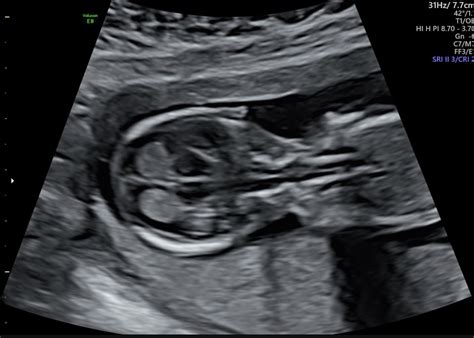

The Nuchal Fold Ultrasound, often referred to as the nuchal translucency (NT) scan, is a non-invasive prenatal screening test. The primary objective of this procedure is to measure the thickness of the nuchal translucency—the clear area of tissue at the back of the fetal neck. All fetuses have some fluid in this area, but a larger-than-normal measurement can sometimes be associated with a higher risk of chromosomal abnormalities such as Down syndrome (trisomy 21), Edwards syndrome (trisomy 18), or Patau syndrome (trisomy 13), as well as certain heart defects.

Timing is everything when it comes to this screening. The Nuchal Fold Ultrasound must be performed within a specific window—typically between 11 weeks and 13 weeks plus 6 days of pregnancy. This window is crucial because the fluid at the back of the neck is easier to measure during these weeks, and the fetus is at a size that allows for high-quality, clear imaging.

• The sonographer uses an ultrasound probe to capture images of the fetus in a sagittal plane (a side-view profile).

• The fetal crown-rump length (CRL) is measured to confirm gestational age.

• The sonographer places precise markers to measure the widest part of the fluid collection at the back of the neck.

• The image is frozen, and the measurement is recorded to the nearest millimeter.